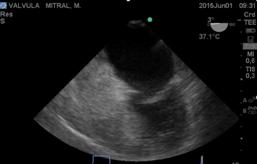

Aunque el equipo quirúrgico puede visualizar la anormalidad valvular anatómicamente, ETE, proporciona una valoración en tiempo real de la fisiopatología valvular; es útil para guiar los procedimientos quirúrgicos de reparación y mejorar sus resultados. ETE, es en la actualidad un monitor clase I, en cirugía de plástica mitral y clase II, en reemplazo valvular(6). La sonda de ETE (Figura1), que avanzando por el esófago llega a medioesofágico(7), mira a la válvula mitral desde un lugar privilegiado, a través de la aurícula izquierda.

La válvula mitral (Figura2), está compuesta por los velos anterior y posterior, de aproximadamente 1 mm de espesor. El velo posterior, se adhiere al anillo fibromuscular mitral en la base, ocupando 2/3 del mismo y tiene forma cuadrangular. Está dividido por 2 hendiduras bien definidas en 3 festones denominados 1, 2 y 3 de anterior a posterior. El velo anterior en forma semilunar, se adhiere al tercio restante del anillo mitral y está en continuidad con el velo no coronario aórtico, también se divide en 3 festones que se corresponden con los festones 1, 2 y 3 del velo posterior.

Figura 2: imagen a 0° transgástrica, eje corto basal de la válvula mitral cerrada y abierta con sus 2 valvas (anterior y posterior) y sus correspondientes 3 velos .